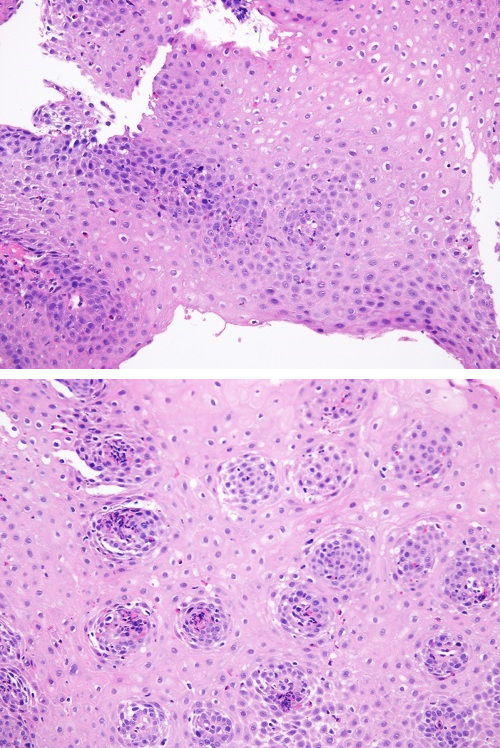

Adolescente de 15 años de edad en revisión en consultas externas de Digestivo Infantil por esofagitis eosinofílica (EEo) desde hace tres años. Clínica de debut en forma de impactación en esófago medio por un trozo de carne, que fue resuelto tras la realización de una endoscopia urgente, en la que se objetivaron estigmas macroscópicos de afectación fibroestenótica. Se documentó la presencia en los tres tercios esofágicos de infiltrado tisular eosinofílico significativo (máximo de 75 eosinófilos por campo; Figuras 1 y 2). El tratamiento con inhibidores de la bomba de protones y corticoides tópicos deglutidos resultó eficaz para atenuar las manifestaciones clínicas, pero ineficaz para revertir la inflamación, pese al buen cumplimiento terapéutico. Se desestimó el tratamiento dietético de exclusión, dada la importante reticencia del paciente a la adherencia al mismo. Se probó posteriormente con dupilumab. Se obtuvo la triple remisión: clínica, endoscópica e histológica (Figuras 3 y 4).

Figuras 3 y 4. Normalización de las biopsias esofágicas tras el tratamiento con dupilumab